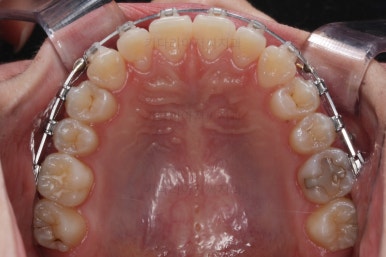

미니스크류를 이용해서 전체 치열을 움직인지 6개월 정도 지난 시점입니다.

교합도 많이 좋아졌고 자연스럽게 중앙선도 맞아졌어요.

미묘한 치열의 사이즈 문제라든지 턱뼈의 비대칭 때문에 맞지 않는 중앙선은 그대로 놔두기도 하지만 왠만하면 잘 맞도록 하는게 좋겠죠?

이제는 디테일한 마무리만 좀 더 하고 치료를 종료하기로 했습니다.

교합도 안정되는 것을 확인했고, 치열도 만족할 수준으로 디테일한 정리를 해줬어요.

왼쪽이 치료 초기의 교합 모습, 오른쪽이 치료 마무리 시점의 교합입니다.

빈틈이 많았던 교합이 많이 개선된 것이 보이시죠?

이러한 이유 때문에 전체교정이 필요했답니다.